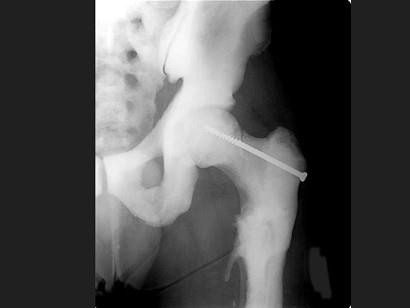

男,37岁,出现多处骨折,结合图像,最可能的诊断是?(?)A.石骨症B.成骨不全C.畸形性骨炎D.转移性骨肿瘤E.氟骨症

问题 男,37岁,出现多处骨折,结合图像,最可能的诊断是?(?)

选项 A.石骨症 B.成骨不全 C.畸形性骨炎 D.转移性骨肿瘤 E.氟骨症

答案 A